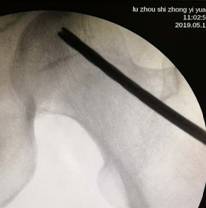

经过术前与麻师团队详尽的讨论及预案制定后,手术医师首先为吴先生实施双侧股骨头坏死髓芯减压,即打开一个像筷子大小的“隧道”孔后,再通过“隧道”将分离的血小板注射进吴先生骨头坏死区域。整个手术仅抽取了80毫升血液,耗时数十分钟,术后三天患者出院。

术中,为患者打通“隧道”,注入血小板